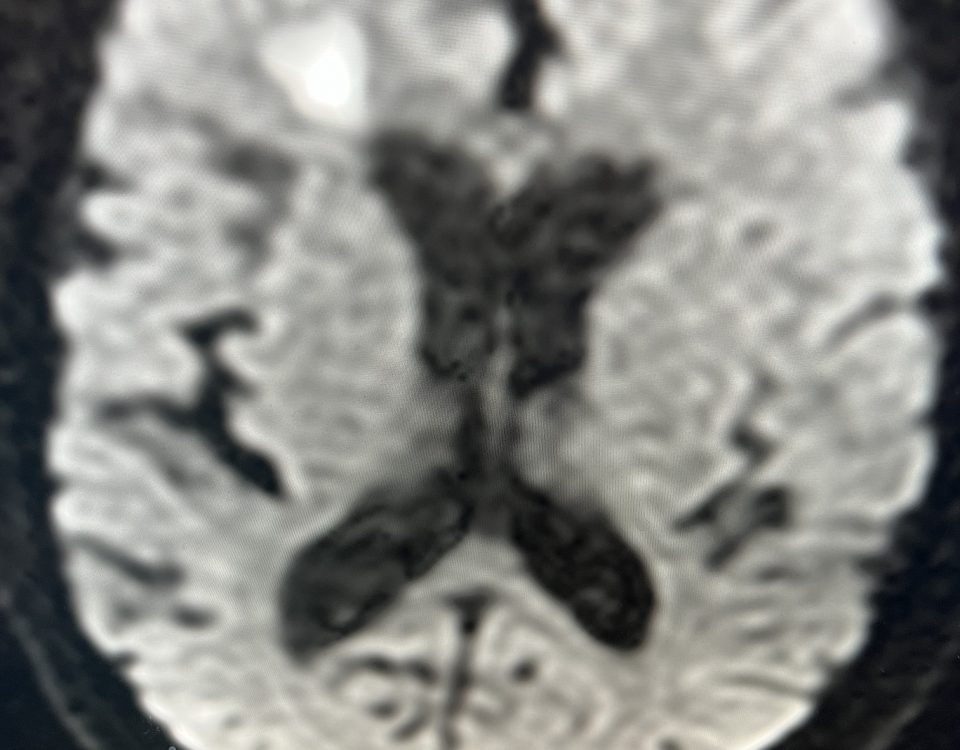

A 55-year-old woman presented with acute onset of severe headache, and possible witnessed seizure. Imaging confirmed intraventricular hemorrhage primarily focused within the fourth ventricle with diffuse […]